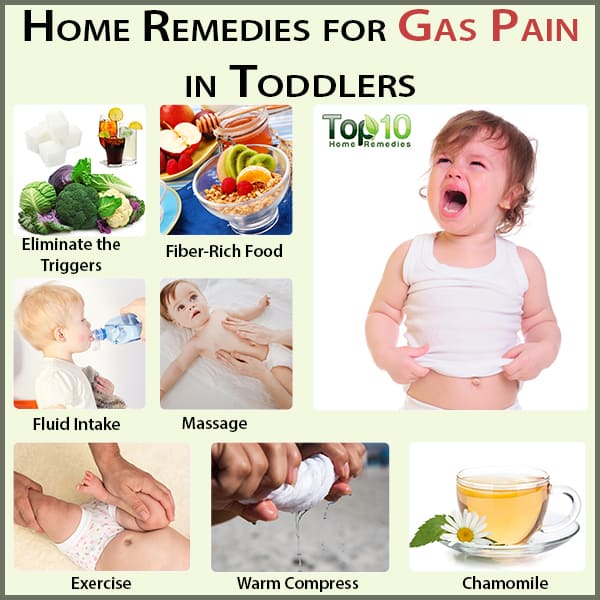

Gas Pain in Toddlers: Causes, Symptoms and Home Remedies | Top 10 Home …